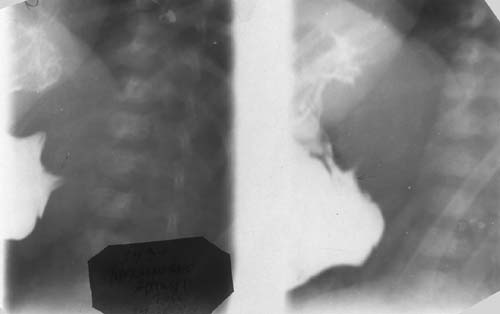

Врожденный пилоростеноз.

Рис. 1. Больной А., 1 мес. Врожденный пилоростеноз. Симптомы «плечиков» и «антрального клюва».